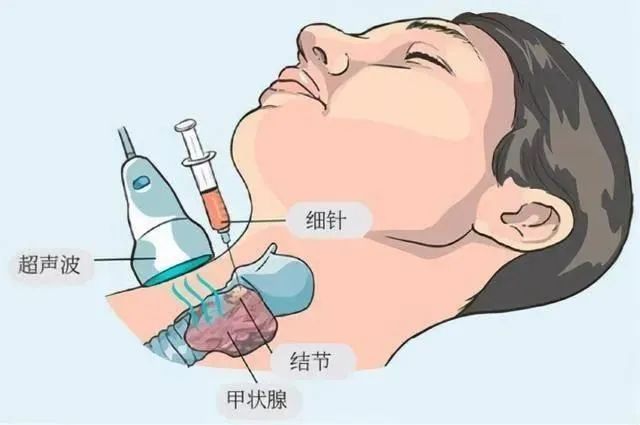

术后动态评估主要包括血清学 (TSH、Tg、TgAb等) 及影像学 (颈部超声、DxWBS、CT、MRI等)的规律复查。